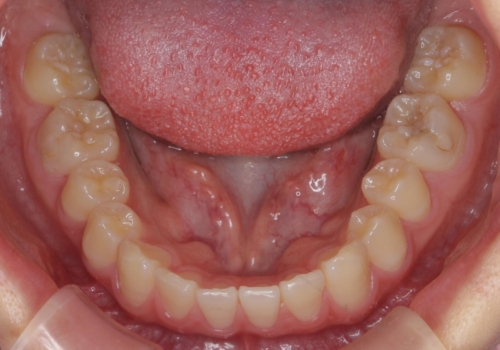

- 10代女性

- ワイヤー矯正

- 9ヶ月

- 前歯のすき間を気にして来院。

全体矯正ではなく部分矯正で治療することになりました。

その代わり、すき間をすべて閉じるのは難しく、両脇の目立たないところに集めて治療終了しています。

低予算、短期間で治療も終了し、大変満足していただきました。

全体矯正をしていないため、就寝時にリテーナー使用は継続していただくことになっています。